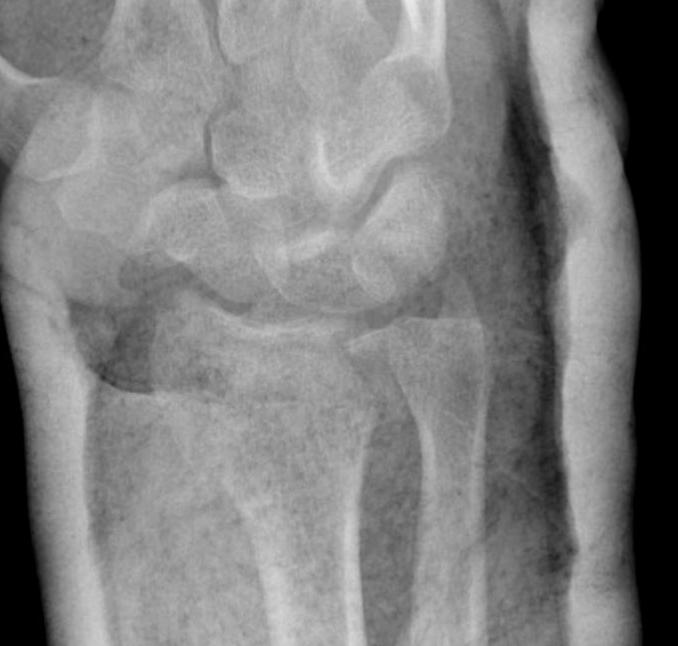

Distal Radius Fracture Articular Step Coronal CTDistal Radius Fracture Articular Step Sagittal CT

Articular incongruency > 2 mm